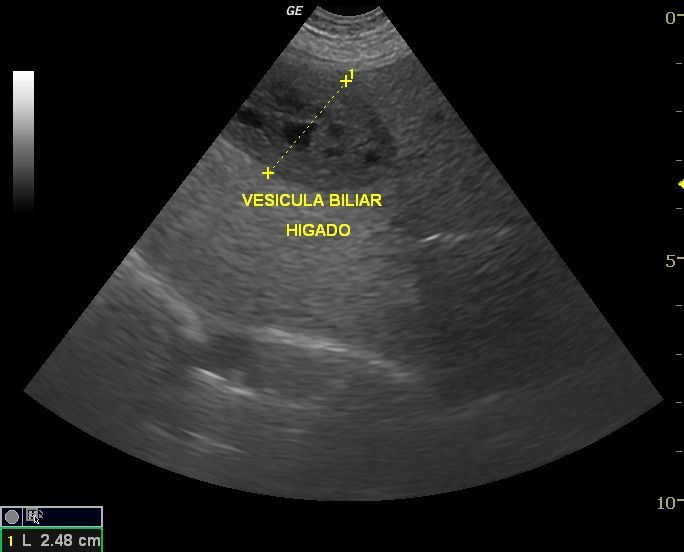

La ecografía es uno de los medios de diagnóstico que más ha evolucionado en los últimos años. Es un método no invasivo, inocuo y que permite dar gran información en muchos campos de la medicina interna, reproducción, oftalmología, y muy especialmente en cardiología.

La Ecografía permite una exploración completa de los distintos órganos aportando datos objetivos para conseguir un diagnóstico preciso , establecer un tratamiento adecuado y realizar un seguimiento de cada caso.

La ecografía como diagnótico de gestación es a día de hoy el método más fiable durante el primer trimestre, además nos aporta datos para predecir la fecha de parto, y realizar un seguimiento del desarrollo de los fetos, pudiendo evaluar el estres fetal.